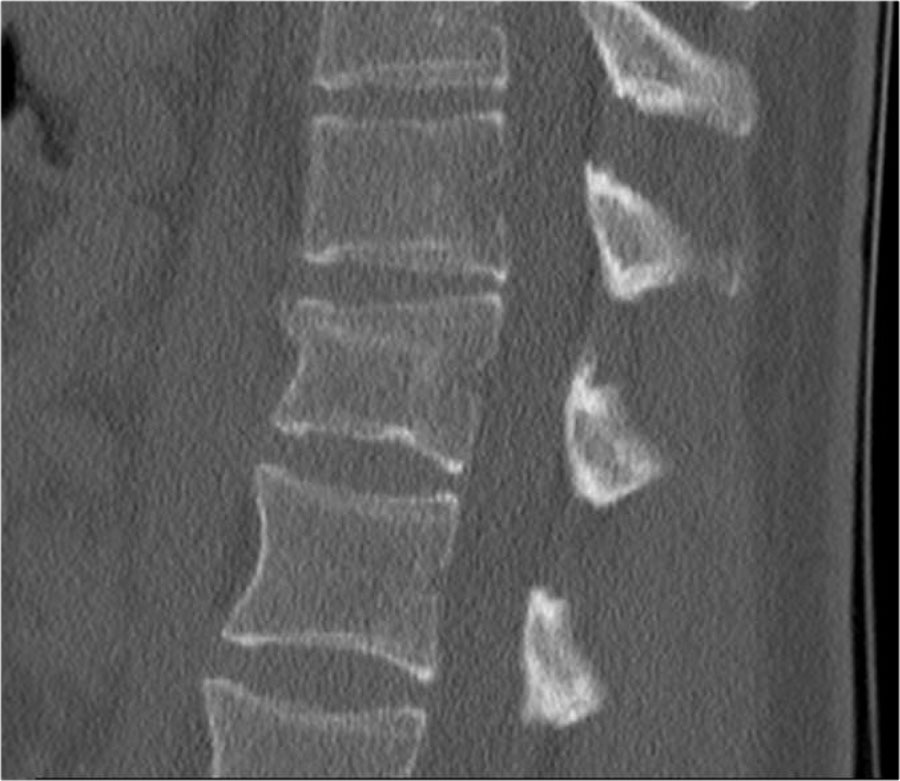

Lưu ý dải tăng tỷ trọng theo chiều ngang, thường được mô tả là xơ cứng (sclerosis).

Dải tăng tỷ trọng này không có nghĩa là tổn thương cũ đang lành với xơ cứng.

Đây đơn thuần là dấu hiệu của sự chèn ép bè xương (trabecular impaction) trong gãy xương cấp tính.

Rất thường gặp trường hợp CT và MRI phát hiện nhiều ổ gãy xương hơn so với X-quang thường quy.

Trong trường hợp này, CT phát hiện 2 ổ gãy và MRI phát hiện 3 ổ gãy.